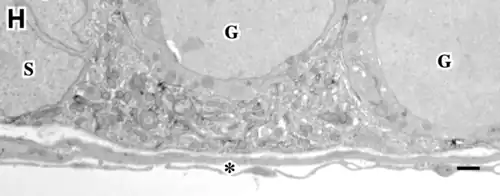

Los túbulos presentan dos compartimentos clásicos: uno basal y otro luminal (o adluminal). Ambos presentan características anatómicas y funcionales diferenciales.[9][10][8][6]

Compartimento basal del túbulo seminífero

Es el área definida entre la lámina basal del túbulo y las uniones estrechas (thigth junctions en inglés), de las células de Sertoli.

- Consta de: una capa de células mioides contráctiles peritubulares, una lámina basal y principalmente de las células de Sertoli. Estas últimas rodean completamente con sus prolongaciones citoplasmáticas a las células germinales y están adheridas entre sí por uniones estrechas en sus membranas.[11]

Compartimento luminal del túbulo seminífero

La disposición anatómica de los elementos de la barrera del compartimiento tubular, impide el contacto directo entre las células inmunocompetentes o sus productos, con las células germinales en diferenciación dentro del adluminal.